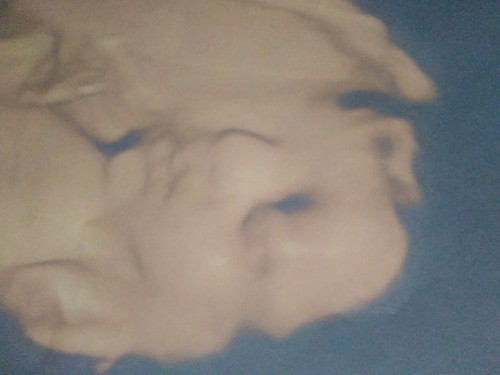

เมื่อหมอปลุกไห้ตื่น หน้าก้อจะประมาณนี้ 29wจ้า